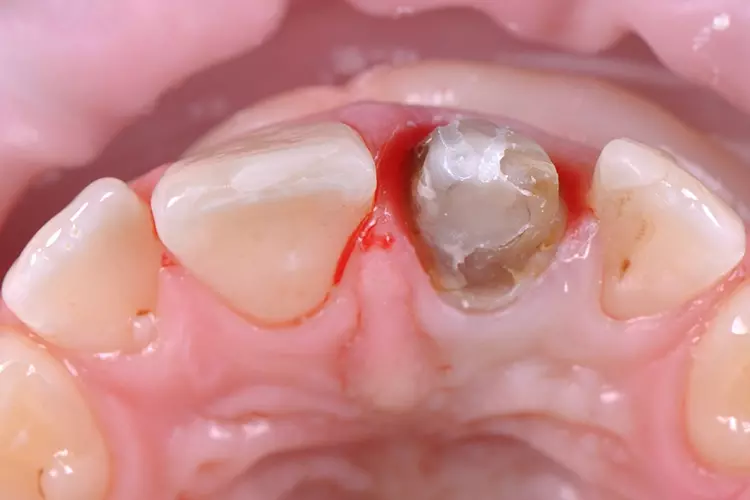

Die vorgefundene Präparation konnte im labialen Bereich in 3 Ebenen anatomisch reduziert und optimiert werden. Bei der Platzierung des zirkulären Präparationsrandes war die „biologische Breite“ nicht berücksichtigt worden und der Kronenrand lag deutlich subgingival.

Die Gingiva wurde mithilfe eines Retraktionsfadens vorsichtig verdrängt und die zirkuläre Präparation mit einer ausgeprägten Hohlkehle klar definiert. Beim Langzeitprovisorium, welches man in der Praxis herstellte, wurden sämtliche ästhetischen und funktionellen Parameter berücksichtigt und die „äußere Hülle“ der definitiven Krone festgelegt.

Zur Realisierung eines möglichst naturgetreuen Behandlungsergebnisses wurde labial ein minimales Cut-back und eine anschließende individuelle Schichtung mit der Verblendkeramik IPS e.max Ceram durchgeführt (Mikroveneering) (Abb. 30–33). Damit der verfärbte Zahnstumpf unter der neuen Zirkonkrone nicht mehr sichtbar ist, wird bei transluzentem Zirkoniumdioxid im Weißzustand auf der Innenseite des Gerüstes ein Opakerliquid aufgebracht. Dieses Liquid trägt nicht auf, da das Material in den Werkstoff eindringt und das Zirkongerüst an den gewünschten Stellen von innen blickdicht, sprich opak, wirken lässt (Fa. BriegelDental) (Abb. 34 und 35).